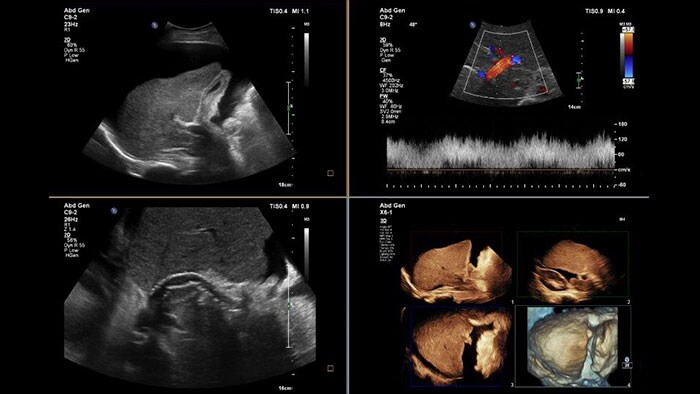

Perform advanced visualization and quantification of ultrasound volume

US Q-App General Imaging 3D Quantification (GI3DQ) provides advanced viewing, manipulation, and quantification of 3D data sets. Perform advanced functions such as MPR interrogation, iSlice tomographic imaging, and volume rendering as well as volumetric measurements using multiple methods including semi-automated tools. Results generated from this tool can be appended to the patient’s exam for complete documentation.

Benefits